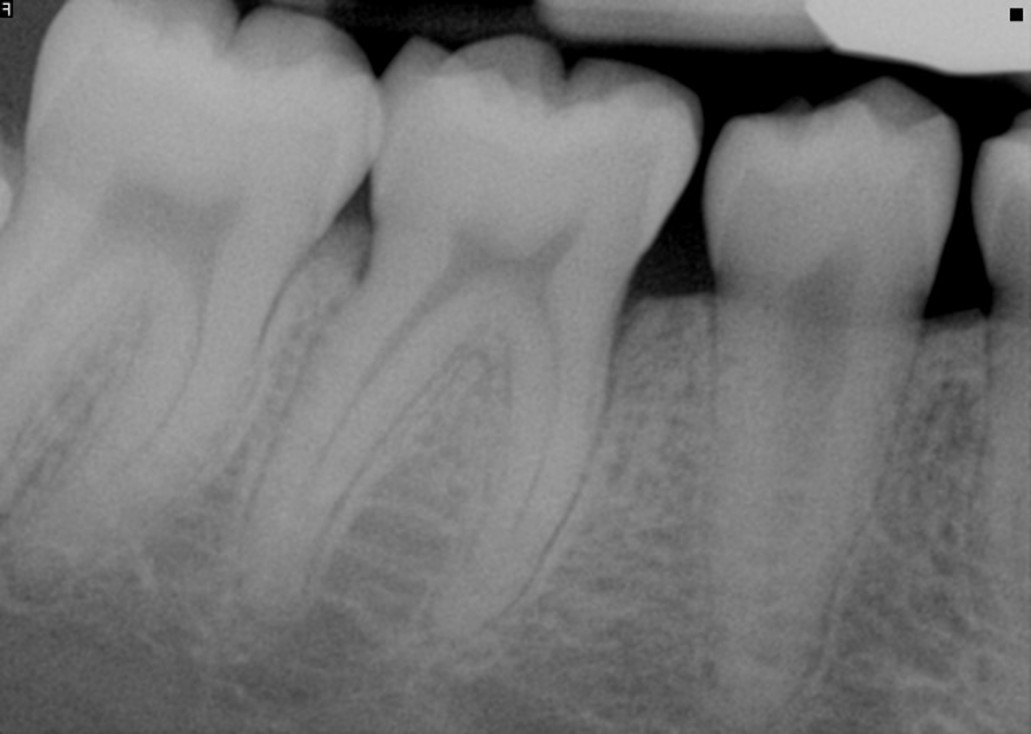

Implant #12

Challenge: Patient presented with severe peri-implantitis on implant #12, exhibiting 50% radiographic bone loss, deep pockets, and inflammation.

Solution: Laser-assisted surface decontamination and regenerative bone grafting to salvage the fixture without explantation.

Outcome: 100% radiographic bone regeneration achieved with complete resolution of inflammation and stable soft tissue attachment.